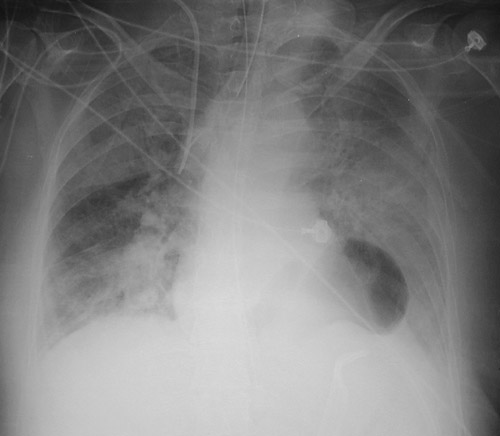

| This AP chest radiograph demonstrates an air-filled structure just above the diaphragm. This is a portion of the stomach that has herniated through the esophageal hiatus, producing a paraesophageal hernia. This is a rare event, but a serious one, because the gastric wall will become infarcted. |